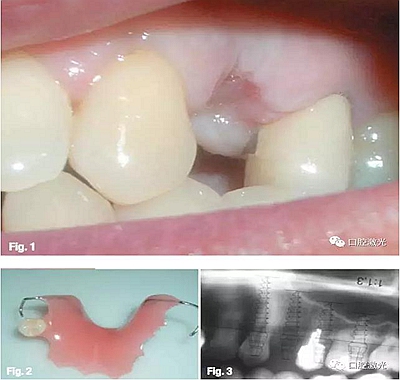

患者基本狀況

患者32歲女性,24根折后佩戴活動(dòng)義齒。六周后,由于感到生活不便,希望安裝固定義齒。通過口腔檢查發(fā)現(xiàn),23和25均存在不適合安裝固定義齒的情況,但符合種植牙的基本條件,遂選擇進(jìn)行口腔種植。